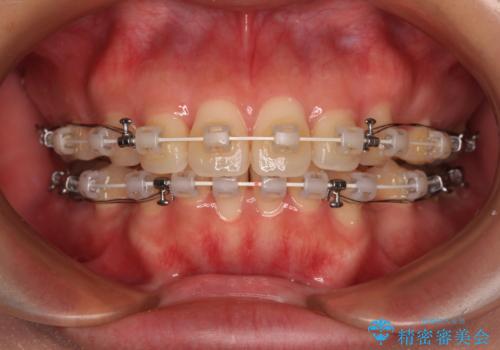

- 全体的なデコボコと口元の突出感を改善したいとのことで来院された患者様です。

このままデコボコを整えるとさらに突出感が増すため、上下左右の第一小臼歯を抜歯し、ワイヤー装置にて矯正しました。

結婚式で途中装置を外した時期がありましたが、2年で治療を終えることができました。